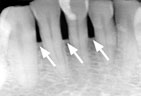

Gum disease is usually caused by plaque, a sticky film of bacteria that constantly forms on teeth. If plaque is not removed with thorough daily brushing and cleaning between teeth, gums become irritated and inflamed. The irritated gum tissue can separate from the teeth and form spaces called pockets. Bacteria move into the pockets where they continue to promote irritation. Left untreated, the process can continue until the bone and other tooth-supporting tissues are destroyed. The early stage of periodontal disease is called gingivitis. It often results in gums that are red and swollen and may bleed easily.

Gingivitis Gingivitis

(bleeding gums)